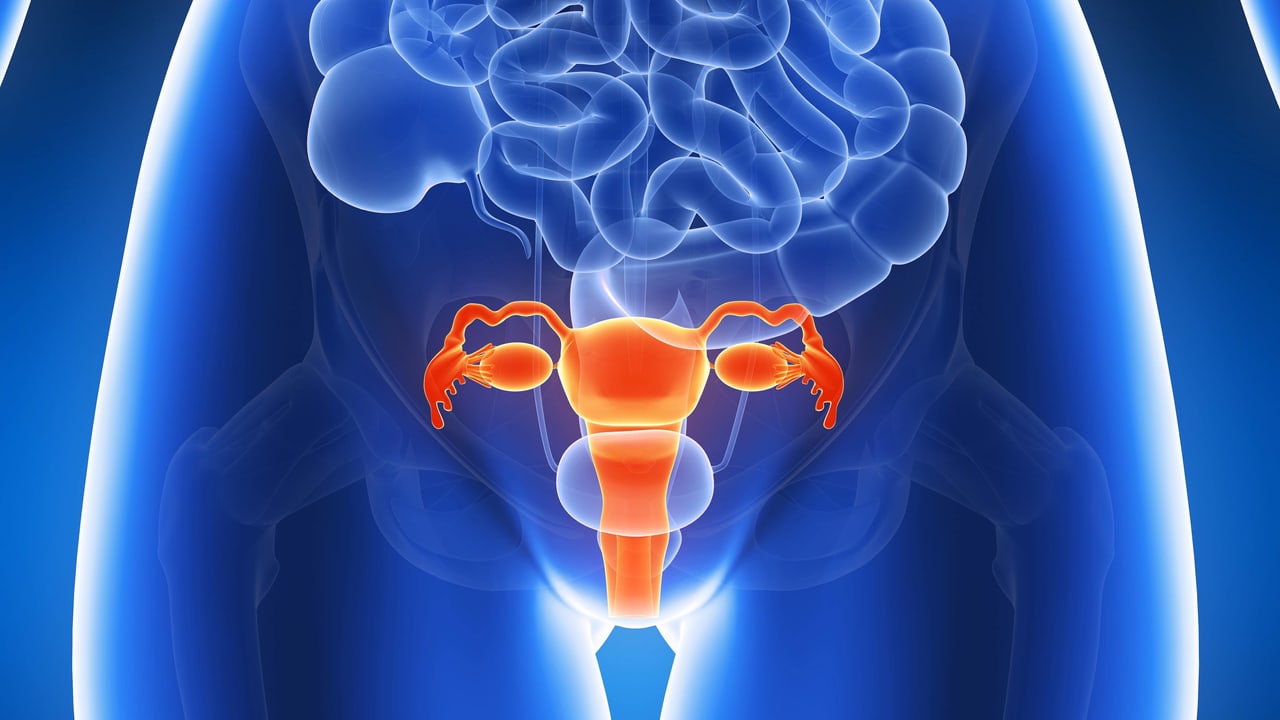

Qu’est-ce qu’un myome ? Un myome est une tumeur qui se développe le plus souvent à l’intérieur ou à l’extérieur de l’utérus et désignée par le nom plus familier de fibrome..

Un « fibrome » de l'uterus encore appelé par les médecins Myome, est une tumeur bénigne faite de la prolifération de cellules musculaires issues de la paroi de l’utérus, cela à -un.

Pourquoi le myome apparaît-il ? Le myome résulte de la prolifération des cellules musculaires de l’utérus. S’il n’existe pas de cause déterminée, le myome est.

Définition. Un myome ou fibrome est une tumeur bénigne se développant à partir de tissu musculaire et de tissu fibreux. La dégénérescence cancéreuse est.

Cette tumeur bénigne affectant environ 50% des femmes âgées de 30 à 50 ans. Aussi appelé fibrome utérin, le fibrome se développe à partir du tissu musculaire.

Le myome est appelé une tumeur bénigne, qui se développe dans les tissus de l'utérus. La tumeur est semblable à la spire noueuse et peut être localisée à la fois sur.

Un myome, communément appelé fibrome, est une tumeur bénigne (non cancéreuse) qui se développe dans ou autour de l’utérus. Les fibromes sont connus sous le nom médical.

Aussi appelé fibrome, le myome utérin est une pathologie gynécologique, généralement bénigne. Elle concerne environ un tiers des femmes en âge de procréer. Cette petite.

Qu’est ce qu’un fibrome ou myome ? Un « fibrome » de l'uterus encore appelé par les médecins Myome, est une tumeur bénigne faite de la prolifération de cellules.

Qu'est-ce qu'un myome ? Le myome, ou fibrome, utérin est une tumeur bénigne de l'utérus qui se développe au sein du muscle lisse. Il n'y a pas de risque que cette.